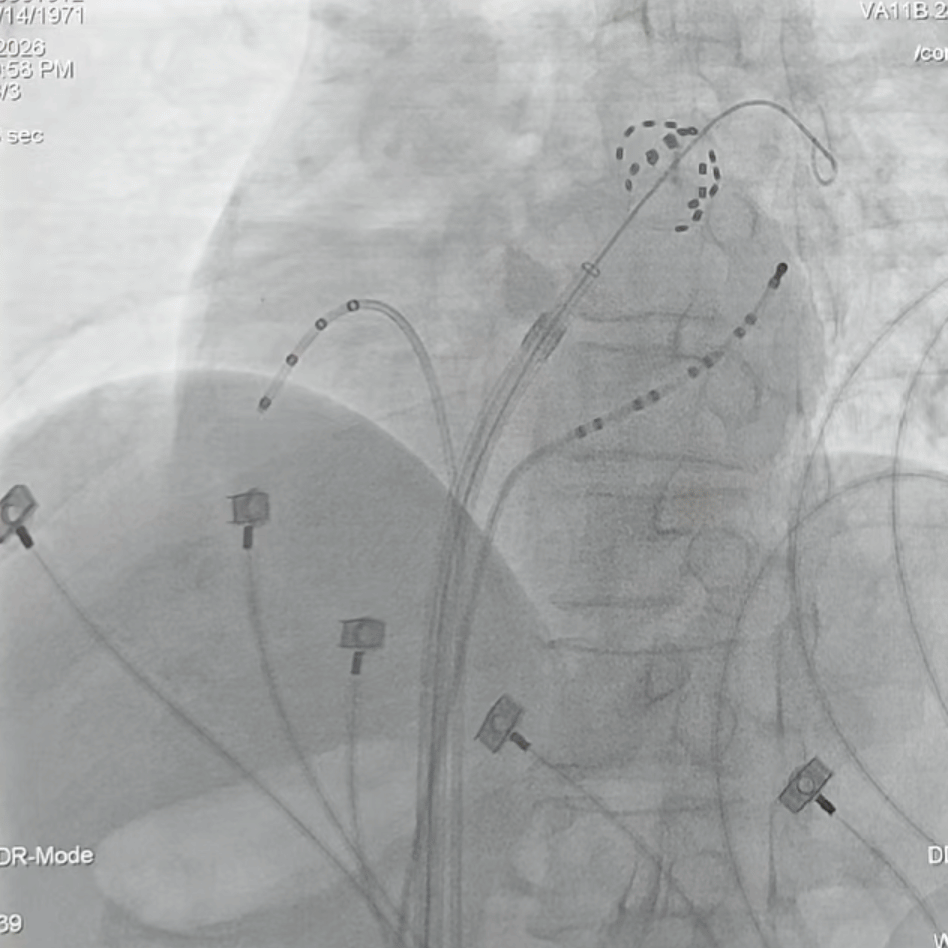

本例患者为阵发性房颤,长期受心慌症状困扰,药物治疗效果不佳。经心血管内科团队全面评估,并与患者及家属充分沟通后,决定采用国际领先的“波科FARAPLUSE脉冲消融系统”进行治疗。整个核心消融过程高效流畅,仅用时36分钟,总放电次数34次,单次放电仅需2.5秒钟,手术效率显著提升。患者术中耐受性良好,生命体征平稳。术后验证显示,所有肺静脉均已达到完全电隔离,消融效果立竿见影,手术获得圆满成功。